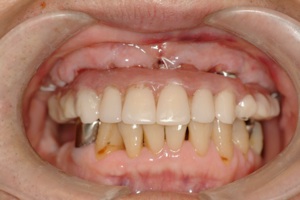

よくないと困るということです。当院で行っているall on 4 は全部仮歯まで一日で行いますので、

一日も歯がないという状態はありません。 この写真の方も前歯しか残っていませんが、インプラント手術当日まで前歯は残しておいて、その当日に抜歯、インプラントを入れて仮歯を固定しています。つまり、歯は一日で入るので、歯が無い、見た目が悪いという状態は全くありませんので、ご心配なく。大分県大分市スマイルライン歯科ではオールオンフォー(all- on- 4)の治療を全国でもいち早く行い数多くの症例を手掛けてきました。そして治療を行ったすべての患者様に喜んで頂いておりますのでご希望の方はまず、CTレントゲンなどで骨の形を診査しますのでお問い合わせください。

その日入った仮歯です、もちろん固定式で、入れ歯のような取り外しは当日から必要ありません。